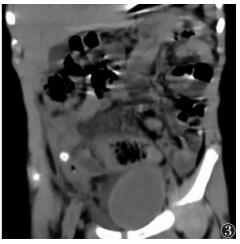

① 9例急性单纯性阑尾炎,MSCT示阑尾管腔均增宽,外径6~9 mm,管腔内多伴少许积液,管壁增厚不明显,管壁边缘及周围脂肪间隙密度模糊,表现为细网线状略高密度影;7例粪石均可显示(图 1),MSCT表现为直径为25 mm的点状或小类圆形高密度影,多位于阑尾根部;伴盆腔积液2例,回盲部周围淋巴结肿大1例。②19例急性化脓性阑尾炎,MSCT示阑尾管腔均增宽,外径8~14 mm;12例伴高密度粪石,当圆形高密度粪石嵌顿在阑尾根部,远端管腔因阻塞常增宽明显;阑尾管壁肿胀,厚度>3 mm,边缘模糊不清,管腔内多伴积液及气泡,6例管腔周围伴脓肿形成,CT表现为高于水样密度影,可伴气泡;4例阑尾脓肿伴穿孔MSCT示2例阑尾局部管壁连续性中断(图 2);5例肠淤张,表现为腹盆部小肠呈不同程度扩张,肠管拥挤,管腔内积气积液;伴盆腔积液14例,肠系膜周围淋巴结肿大2例。③16例急性坏疽性阑尾炎,MSCT示阑尾管腔不同程度扩张,外径7~18 mm,管壁明显增厚(图 3);4例局部管壁连续性中断,管腔周围可伴脓肿及气泡;14例管腔内伴圆形高密度粪石,管腔内积气、积液;9例管壁周围脂肪密度可见条状、片状增高,邻近回肠末端及盲肠管壁增厚;6例肠淤张;伴腹盆腔积液10例,肠系膜淋巴结肿大4例。

| 图 3 男,3岁,急性坏疽性阑尾炎,阑尾外径明显增宽,管壁明显肿胀,管腔内结石,盲肠壁增厚,盆腔积液 |